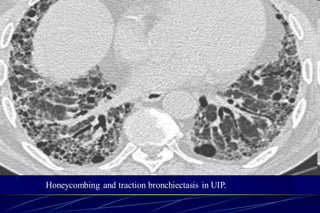

HONEYCOMBING

Defined as - small cystic spaces with irregularly

thickened walls composed of fibrous tissue.

Predominate in the peripheral and subpleural

lung regions

Subpleural honeycomb cysts typically occur in

several contiguous layers. D/D- paraseptal

emphysema in which subpleural cysts usually

occur in a single layer. 62

Honeycombing is defined by the presence of small cystic

spaces with irregularly thickened walls composed of fibrous

tissue.

HRCT showing

subpleural

broncheolectasis

Honeycombing and traction bronchiectasis in UIP.

Typical UIP with honeycombing and traction

bronchiectasis in a patient with idiopathic

pulmonary fibrosis (IPF)